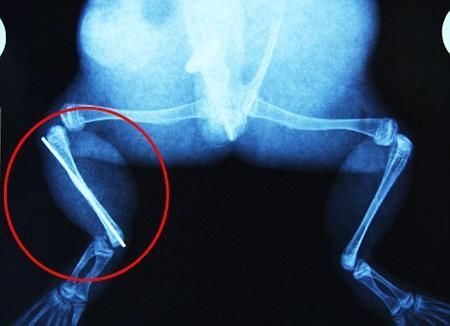

環(huán)球網(wǎng)4月2日報道 據(jù)《每日郵報》報道,上個月,南非大牛蛙布魯萊的右小腿被鄰居家的一只狗咬到,導(dǎo)致粉碎性骨折,現(xiàn)在經(jīng)過2個小時的手術(shù),它的斷腿已經(jīng)被接上,它也因此成為有史以來第一只通過外科手術(shù)用鋼針接上斷腿的青蛙。

野生生物專家安妮經(jīng)常為學(xué)校寫教材,她認(rèn)為這是人類第一次通過手術(shù)給一只青蛙接斷腿。在手術(shù)開始階段,獸醫(yī)把少量給狗用的麻醉藥注入到這只青蛙體內(nèi),讓它失去知覺。然后他在布魯萊的斷腿上切開一個小口,把一根小鋼針植入腿里。最后獸醫(yī)給它縫了9針,把切口縫合在一起。僅僅幾周后,布魯萊就能在安妮家附近活動了。這只青蛙大約已有25歲,主要以嚙齒動物、蛇和其他青蛙為食。布魯萊所屬的牛蛙種群正在不斷減小,目前只能在非洲南部的濕地里才能看到這種青蛙。

布魯萊的主人,居住在南非約翰內(nèi)斯堡附近的62歲的安妮·米恩斯說:“我對這只青蛙如此關(guān)心,人們一定認(rèn)為我瘋了,但是我無法眼睜睜看著它那么痛苦。青蛙因其靈活的腿腳而著稱,一想到布魯萊的腿里要留下一個薄金屬片,我就感到心痛。然而我知道,如果不進(jìn)行手術(shù),布魯萊以后就沒辦法動彈了。因此我匆匆趕到獸醫(yī)那里,央求他給這只可憐的青蛙動手術(shù)。這位獸醫(yī)整天救助小貓小狗,他很難理解為什么我這么擔(dān)心一只青蛙,但是最終他還是答應(yīng)了給布魯萊做手術(shù)。手術(shù)后是幾個小時的焦急等待,我們希望它能快快蘇醒過來。不過現(xiàn)在它的傷口已經(jīng)愈合,又能在花園里跳來跳去了。X光照射顯示,它會恢復(fù)的跟以前一樣!